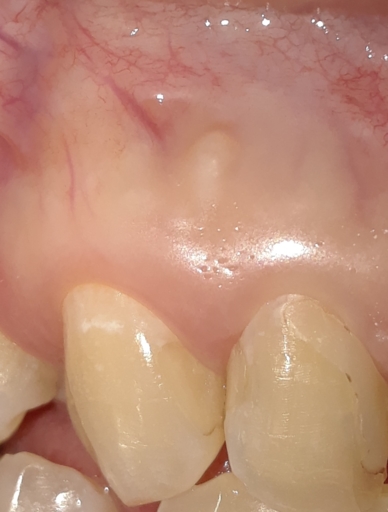

I had a RC (upper central incisor) done in the early 80s and have recently (last 15 years) experienced pain when eating/drinking hot liquids. I avoided them and the symptoms largely vanished. However, more recently (last 2 years), I have pain on palpation extending upwards into the opening of my nose and the tooth feels less secure. I am wondering if I need a RC retreatment or an apico. Can you help with the rough diagnosis and tell me what you think I should be doing at this time? Thanks in advance.